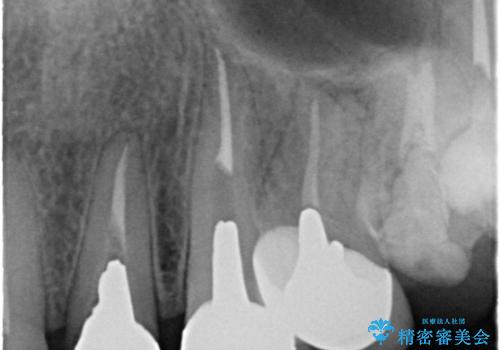

- 全体的な治療と、見た目をきれいにしたとのご希望で来院されました。

上顎の前歯はガタガタがあり、過去に治療した歯はつぎはぎのようになっており、審美的に周囲と調和がとれていない状態でした。

治療計画としては

①仮歯を装着

②矯正治療

③セラミック装着

の順で行いました。